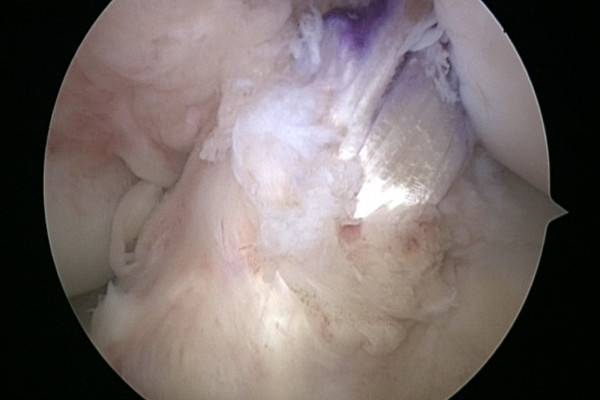

Ist das Kreuzband vollständig abgerissen ist eine Heilung ohne Operation nicht möglich. Um das Kreuzband dennoch zu erhalten kommt die Ligamys® Technik oder „Dynamische Intraligamentäre Stabilisierung“ zum Einsatz. Hierbei wird das abgerissene Kreuzband über eine wenig Millimeter messende Bohrung mit Nähten wieder am Oberschenkelknochen fixiert. Um die Naht in der Zeit der Heilung zu schützen wird eine stabile Kordel als innere Schienung parallel zum Kreuzband gespannt. Diese Kordel wird im Unterschenkelknochen im eigentlichen Ligamys® Implantat verankert. Hier sorgt eine Feder dafür, dass die Kordel über das gesamte Bewegungsausmaß die selbe Spannung behält. Der gesamte Eingriff wird im Rahmen einer Kniegelenksspiegelung also ohne weite Eröffnung des Kniegelenks durchgeführt.

Zur Durchführung dieses Eingriffes ist lediglich eine Kniegelenksspiegelung und keine langstreckige Eröffnung des Kniegelenkes erforderlich.